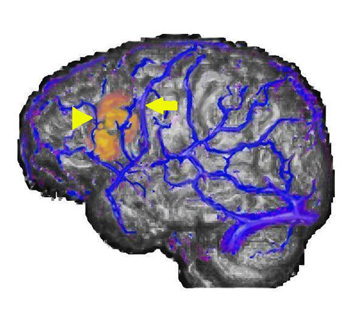

Caso 1

Mujer diestra de 27 años de edad sometida a IMR y VRM para descartar una lesión estructural. La paciente se ofreció voluntariamente para realizar una tarea de generación de verbos.

Imagen de representación triple. Vista lateral izquierda de IRM, VRM e IRMf

La imagen muestra la fusión de los tres procedimientos diferentes. La representación volumétrica del cerebro obtenida de la secuencia de IRM se observa en una escala de grises. La imagen de las venas superficiales y el seno del hemisferio izquierdo obtenida mediante la VRM se observan en color azul. La activación obtenida de la secuencia ecoplanar usada para la IRMf se muestra en color amarillo y rojo.